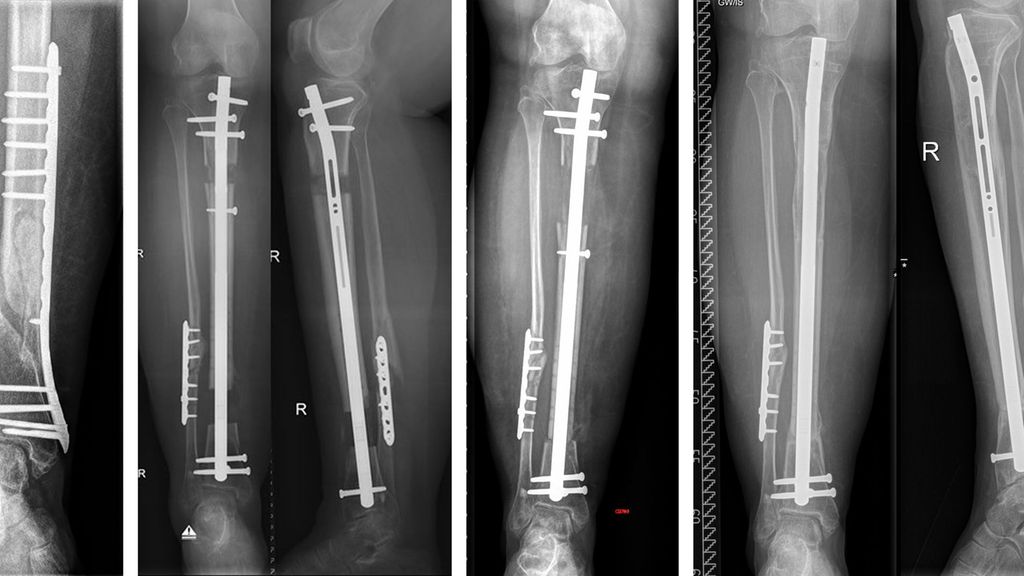

Abb. 4: Patient, männlich, 28 Jahre, St. p. 3-gradiger offener Oberschenkelfraktur links, 8 Monate postoperativ: Infektpseudarthrose (a); 1. Operation: Débridement, Zementspacer, temporäre Stabilisierung mit Platte (b); Z. n. 2. Operation: Implantation Segmenttransportnagel, laufender Transport (c); 1 Jahr postoperativ: Patient ist beschwerdefrei, Docking-Site verheilt (d)

Abb. 5: Patientin, weiblich, 42 Jahre, 2-gradig offene distale Unterschenkelfraktur rechts (auswärts versorgt). Im Verlauf zeigten sich eine zunehmende Valgusfehlstellung und fehlende Heilung im Sinne einer atrophen Pseudarthrose. Die Patientin gab ausgeprägte Schmerzen und fehlende Belastbarkeit an, die Infektparameter waren negativ. Im präoperativen Ganzbeinröntgen zeigte sich eine Valgusfehlstellung von 20°, welche mittels Segmenttransportnagel nach exakter Planung korrigiert werden sollte (a); Resektion der Pseudarthrose und Implantation des Segementtransportnagels sowie Korrekturosteotomie bei in Fehlstellung verheilter Fibula, laufender Transport (b); Docking und Belastungsaufbau nach 4 Monaten. Proximal zeigt sich ein schöner Distraktionskallus (c); Ergebnis 8 Monate postoperativ: sowohl Segmenttransport als auch Dockingsite konsolidiert. Die proximalen Verriegelungsschrauben wurden bei störenden Schraubenköpfen entfernt. Die Patientin ist beschwerdefrei und uneingeschränkt mobil (d)